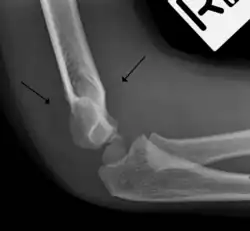

In children, a posterior fat pad sign suggests a condylar fracture of the humerus. In adults it suggests a radial head fracture.

The posterior fat pad is normally pressed in the olecranon fossa by the triceps tendon, and hence invisible on lateral radiograph of the elbow.[3] When there is a fracture of the distal humerus, or other pathology involving the elbow joint, inflammation develops around the synovial membrane forcing the fat pad out of its normal physiologic resting place. This is visible as the "posterior fat pad sign" and is often the only visible marker of a fracture, particularly in the pediatrics population.